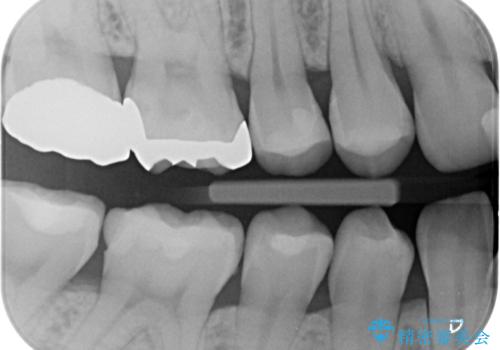

- 奥歯が虫歯になっていたため治療しました。

手前側の歯は前から見えるため、セラミックの詰め物で治療しました。

奥は高さを取るのが難しかったため薄く作れる金属(ゴールド)で治療しています。

- 合計 26.4万円(内訳:右上7 PGAクラウン 11万円(旧料金)、右上6PGAインレー 7.7万円(旧料金)、右上5 emaxインレー 7.7万円)費用は治療当時の料金となります